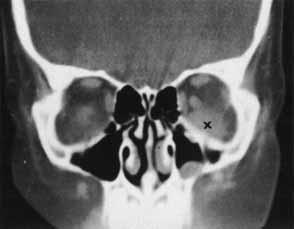

Hemorrhage can be localized to the subperiosteal potential space, extraconally, or intraconally within the orbital soft tissue, or within the belly of extraocular muscles. The condition can be associated with pain, nausea, diplopia, or decreased vision. The more obvious finding might be lid ecchymosis and edema but requires further examination for retroseptal signs. There may be conjunctival chemosis or expanding ecchymosis. Clinical findings reflect the mass effect of accumulating blood within the confines of the bony orbit and orbital septum (Fig. 2). Subperiosteal hematomas are usually restricted by the tight adherence of the periosteum to the orbital bone except in areas, such as suture sites, where this association is weakest. Hemorrhage localized to the muscle sheath may cause selective extraocular muscle restriction that requires radiologic studies to distinguish it from incarceration into a fracture site (Fig. 3). Localized bleeds within the orbital soft tissue can produce proptosis or dystopia. Diffuse hemorrhage may limit eye movement globally and increase retropulsive resistance. Increased intraorbital pressure on the globe and optic nerve may cause elevated intraocular pressure, choroidal folds, compressive retinal vascular compromise, or optic neuropathy, so maintaining vigilance for progressive, potential, vision-threatening situations is important.

Fig. 3 CT scan of inferior orbital hematoma (X) involving the inferior rectus muscle and causing severe upgaze and moderate downgaze limitation.